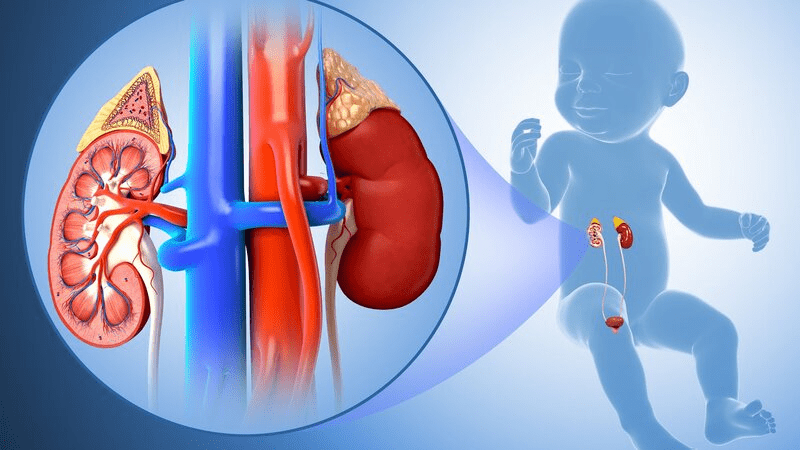

Did you know that 1 in 7 American adults—that’s over 37 million people—are living with chronic kidney disease right now, yet 9 out of 10 have no idea their bodies are quietly struggling?

Turning 35 or 40 often sneaks in unexpected hurdles—like that extra tiredness after meals or the way your shoes feel tighter by evening. According to the National Kidney Foundation, 1 in 3 U.S. adults is at risk for kidney issues, and everyday stresses like skipped water breaks or quick processed snacks pile up fast.

Your kidneys filter hundreds of liters of blood daily, and plain water is their best friend for moving waste efficiently. Research from WebMD and the Mayo Clinic shows even mild dehydration over time forces them to work harder, impacting everything from energy to comfort.